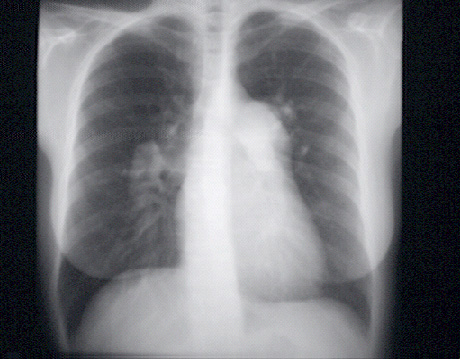

You are incorrect - our patient's chest X rays show left atrial enlargement and right ventricular enlargement.

These chest X rays show a markedly dilated pulmonary artery.

In this PA view, it is demonstrated just beneath the aortic knob at the upper left sternal border. Note that the dilated pulmonary artery tapers rapidly. This has been called “pruning” and is typical of severe pulmonary hypertension.